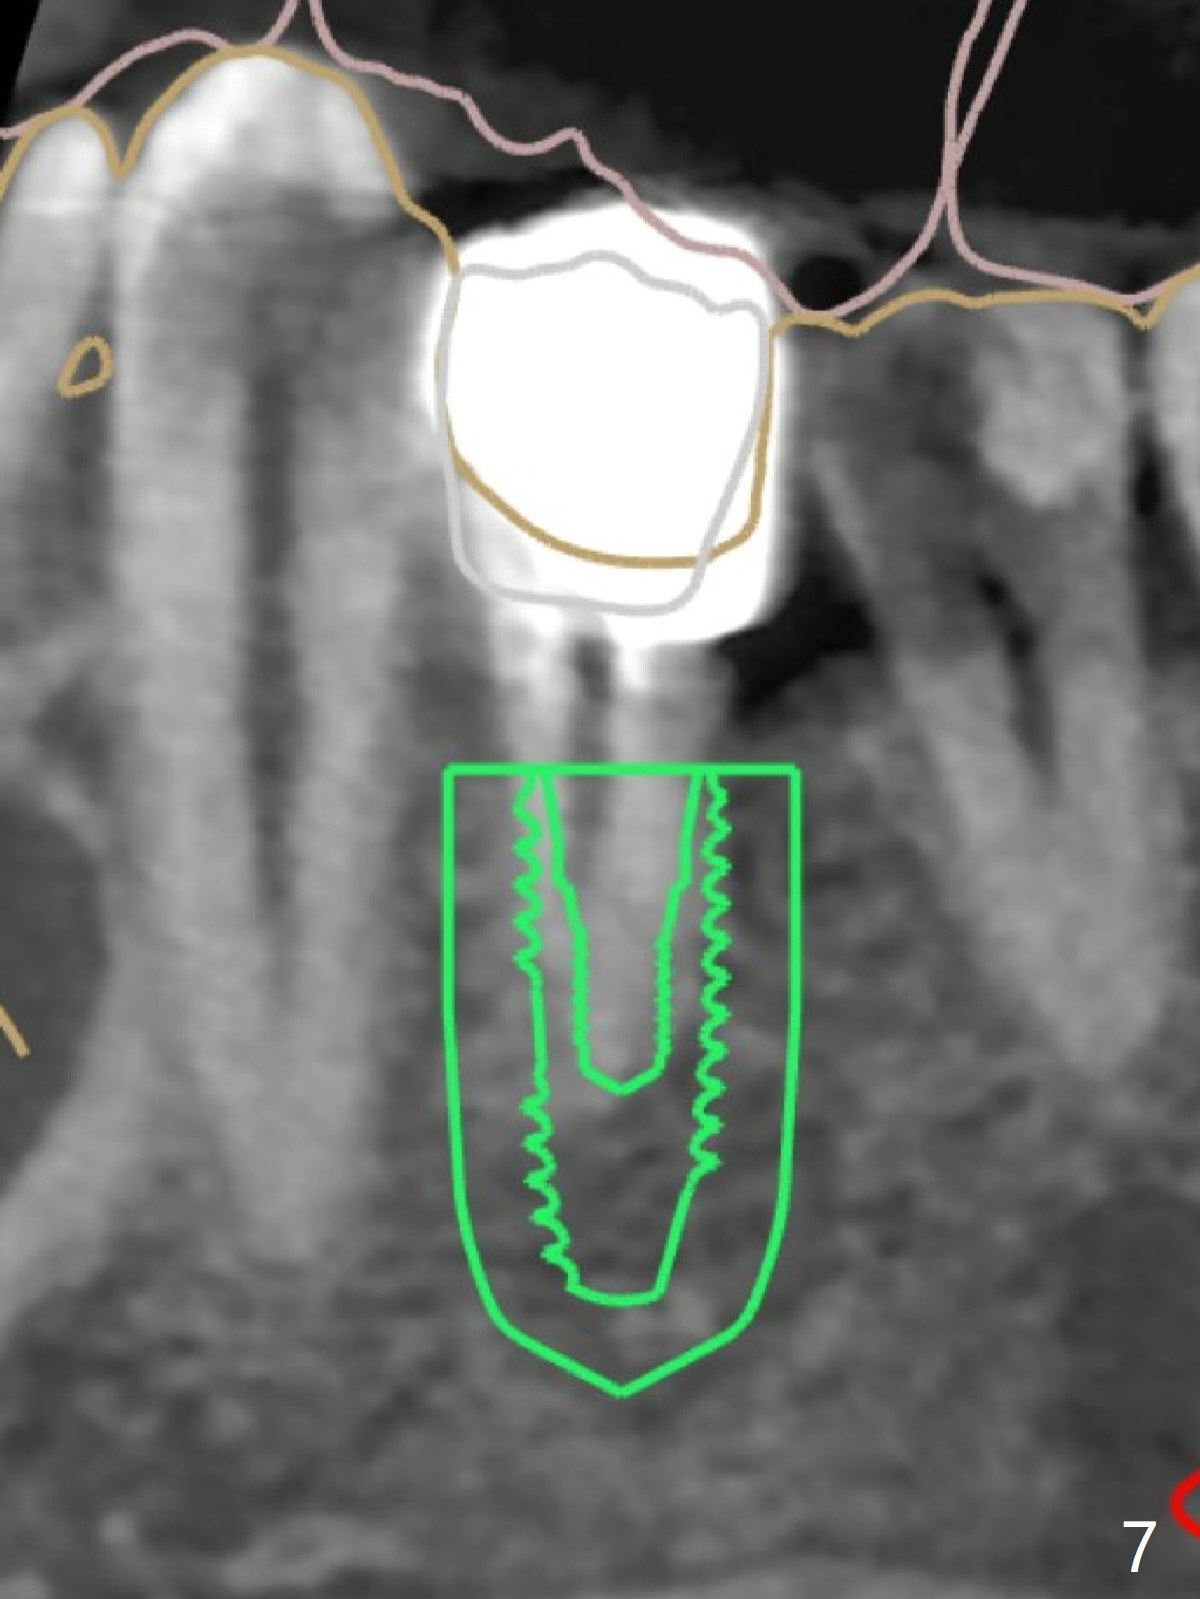

A 42-year-old man has been our patient for 3-4 years (Fig.1). An asymptomatic fistula develops lingual to the tooth #21 (Fig.2). An oblique fracture line appears to be next to a post (Fig.3 ^). A 3.5x11.5 mm implant seems to be able to be placed immediately lingual to the thick lingual plate with guide (Fig.4 L). No buccal deviation will occur with sufficient buccal gap. Design of an immediate implant at #21 (coronal section, Fig.5). In fact the root remains in place first (i.e., extract the crown first, Fig.5'). When osteotomy is done with the last drill 4x11.5 mm, there will be no deviation because of even counteraction between the buccal root and the lingual plate (Fig.6'). Then the root will be removed. But the 4.5x11.5 mm implant may be deviated buccal because of implant engagement into the lingual plate without buccal counteraction. Therefore, a 4x13 mm implant will be placed following 3.5x13 mm (last) drill. The implant is placed between the mesial and distal walls (Fig.7 sagittal section).